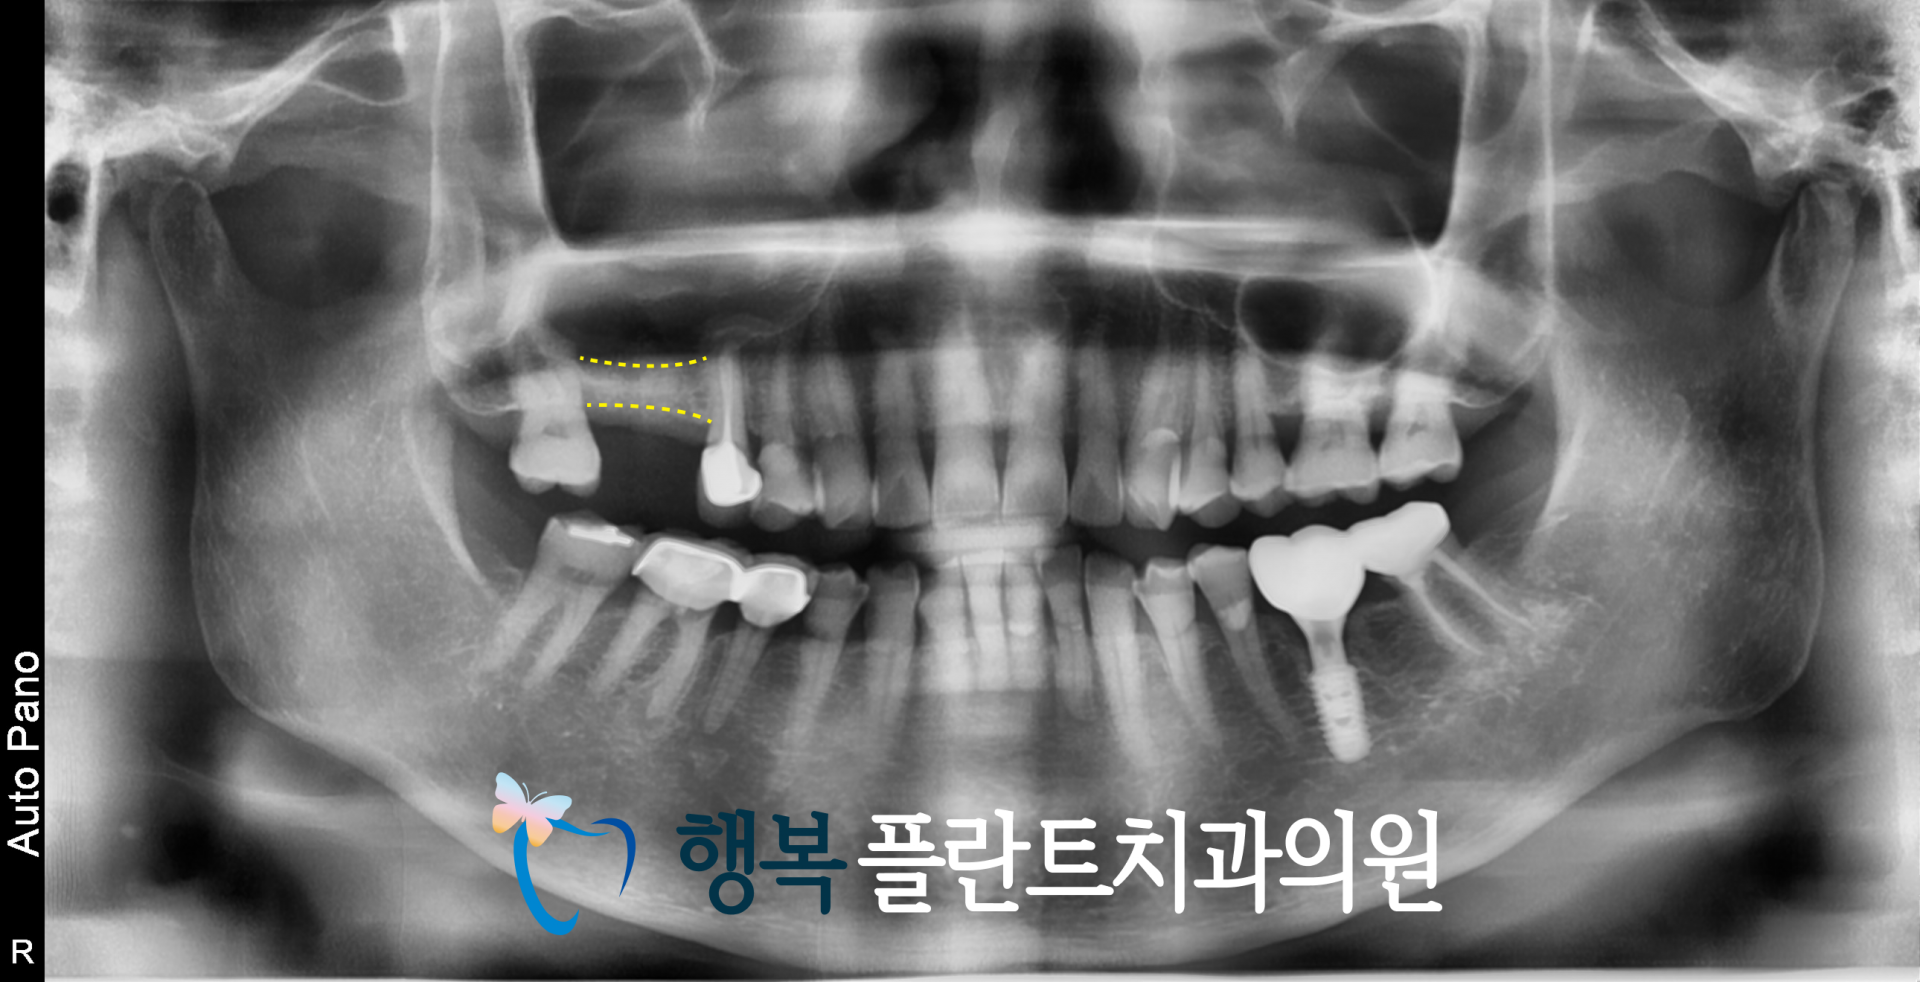

따라서 우선 발치와 보존술을 통해 추후 임플란트를 위한 기반을 최대한 지켜주는 방향으로 치료를 진행했습니다.

발치와 보존술은 발치 부위에 인공뼈를 이식하여 뼈의 재생을 돕는 치료입니다.

위와 같은 케이스의 경우 발치 직후 아무 처치 없이 시간을 보내게 되면 잇몸뼈가 생각보다 빠르게 줄어들 수 있기 때문에

이후 식립 위치와 방향까지 고려한 준비가 중요하며 발치와 보존술을 이를 위한 과정이라고 볼 수 있습니다.

[발치와 보존술로 최대한 잇몸뼈를 보존]

그렇게 3개월간 치유를 기다린 뒤 다시 CT를 확인해 보니 발치와 부위의 회복은 안정적으로 이루어지고 있었지만

상악동의 영향으로 인해 임플란트를 식립하기에는 여전히 수직적인 골 높이가 다소 부족한 상태였습니다.

[임플란트를 심기에는 여전히 부족한 뼈]